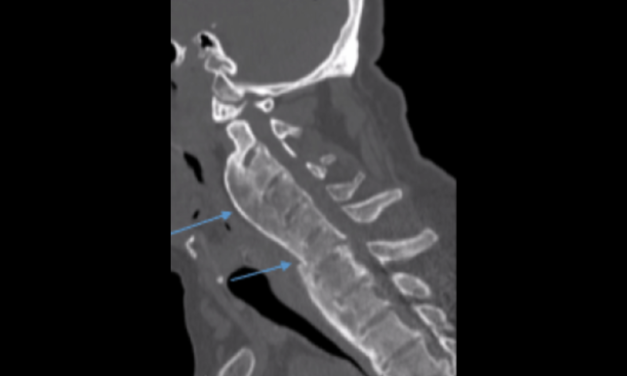

Top 5 Masqueraders of Osseous Disease on Radiographs

Unfamiliar radiographic findings can alarm clinicians and lead to unnecessary testing. This guide reviews five common, non-pathologic osseous variants to improve diagnostic confidence and patient care.